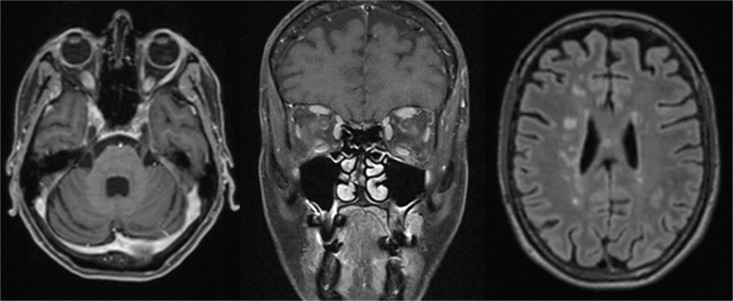

Case presentation: We narrate all reported cases of TA in patients with MS and report the case of a 57-year-old woman with MS with suspected bilateral optic neuritis and typical contrast-medium enhancement in both optic nerves. Because of normal visual acuity on both eyes, malignant hypertension, and fundoscopic findings indicative of hypertensive retinopathy, we diagnosed hypertensive retinopathy with secondary contrast-medium enhancement of the optic nerves. We established antihypertensive medication and searched for secondary causes of hypertension and highly elevated erythrocyte sedimentation rate, which led to the finding of large vessel wall inflammation and the diagnosis of TA.